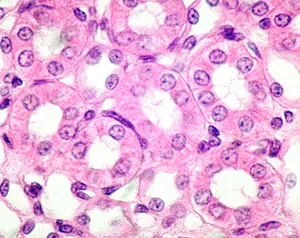

Simple Cuboidal - Secretion Specialists

- Single layer of cube-shaped cells with a central, spherical nucleus.

- Primary Functions: Secretion and absorption.

- Kidney tubules (e.g., Proximal Convoluted Tubule)

⭐ In the kidney's Proximal Convoluted Tubule (PCT), these cells feature dense apical microvilli (brush border), which massively increases the surface area for nutrient and water reabsorption.